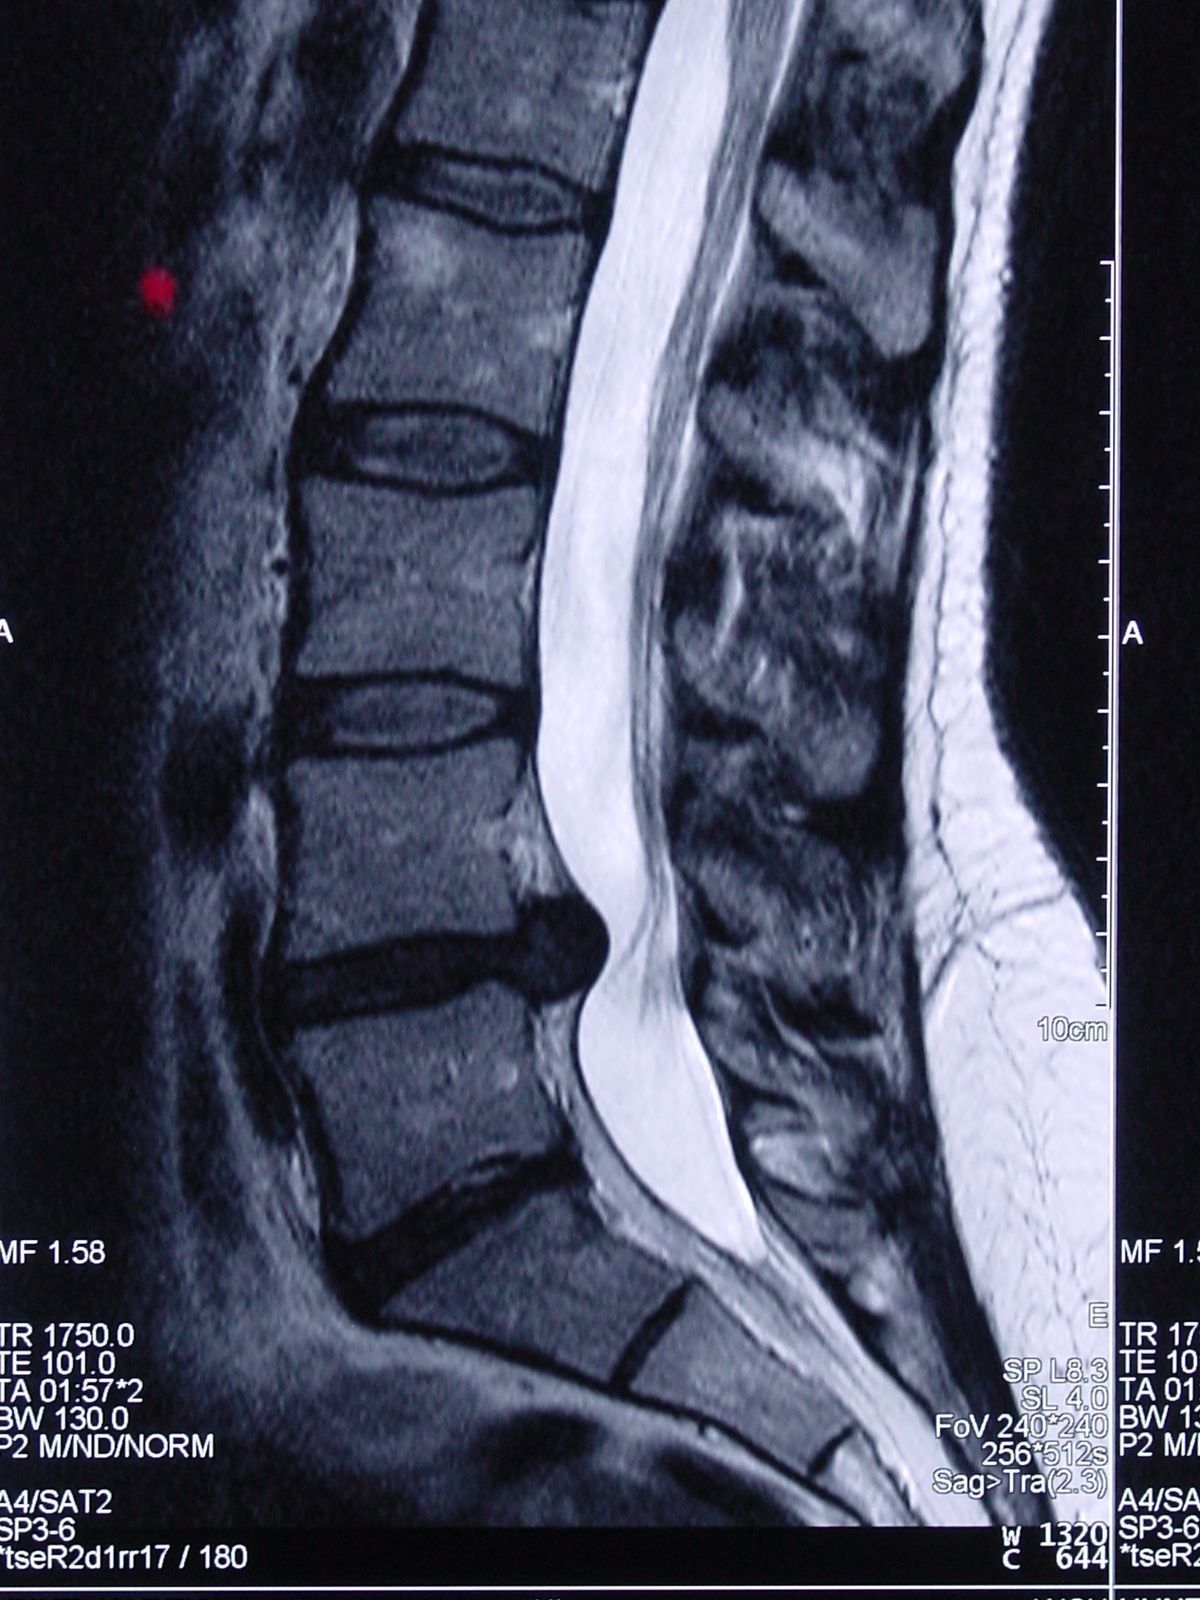

At your first visit, your doctor may recommend an x-ray or MRI to pinpoint the specific areas of damage and discomfort. Using this information, your doctor will determine your course of therapy and whether you are a candidate for Spinal Decompression (SD).